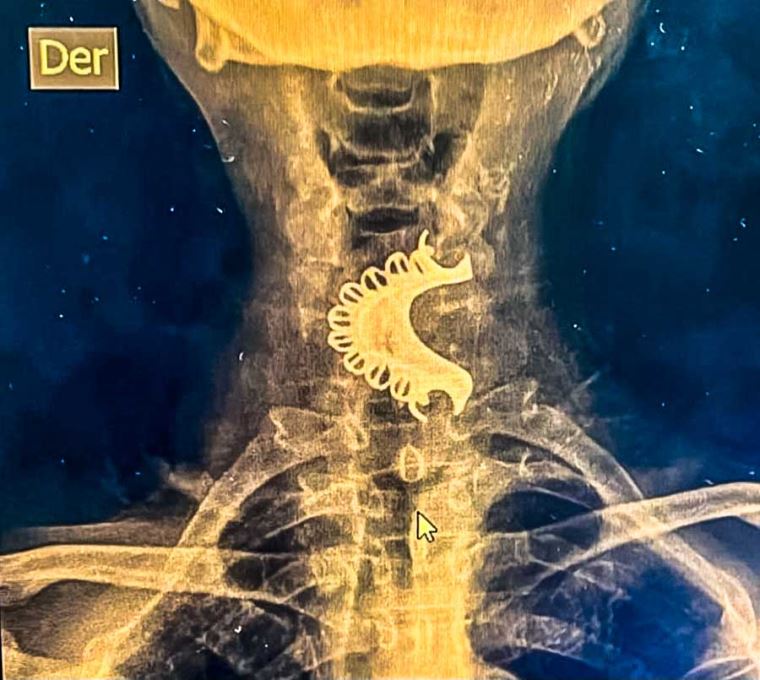

Por su parte, el doctor Raúl Maurtua, cirujano de cabeza y cuello del Hospital Sabogal, informó que el paciente presentó dolor y dificultades para respirar durante cuatro días antes de acudir al Hospital Gustavo Lanatta de Huacho. Allí, una radiografía cervical reveló que la dentadura postiza estaba alojada en la hipofaringe, ubicada en la parte inferior de la garganta, justo detrás de la laringe y antes del esófago.

Debido a la gravedad del caso, el paciente fue referido al Hospital Sabogal, donde recibió atención inmediata. Se convocó una junta médica interdisciplinaria conformada por especialistas en cirugía general, gastroenterología y emergencias, quienes determinaron realizar una endoscopia digestiva alta en sala de operaciones para retirar el cuerpo extraño.

“El procedimiento fue realizado por un gastroenterólogo, mientras que el cirujano de cabeza y cuello utilizó pinzas especiales para extraer la dentadura. Posteriormente, el paciente fue trasladado a sala de recuperación y, días después, dado de alta”, explicó el doctor Maurtua.